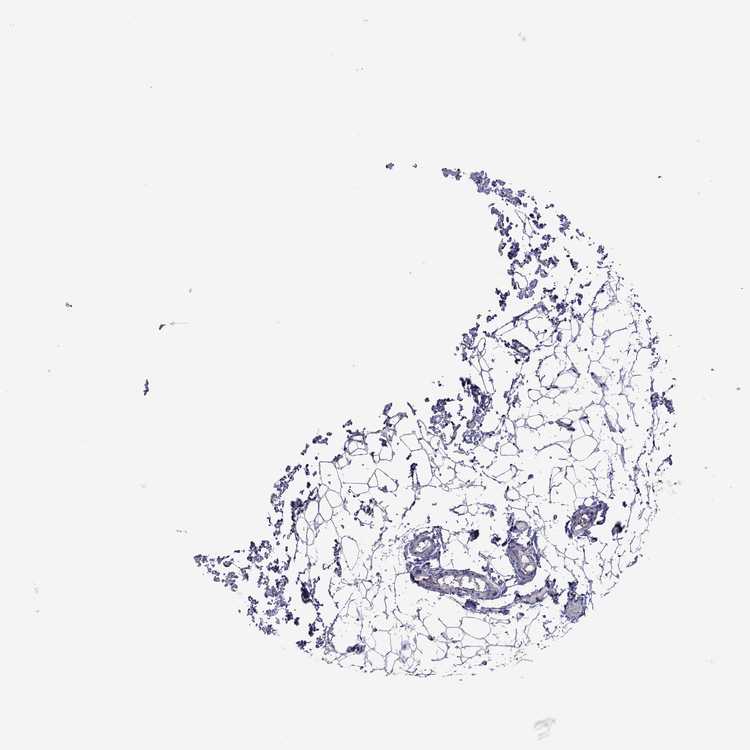

LYMPH NODE - Antibody stainingi

Antibody staining in the annotated cell types in the current human tissue is reported as not detected, low, medium, or high, based on conventional immunohistochemistry profiling in selected tissues. This score is based on the combination of the staining intensity and fraction of stained cells.

Each image is clickable and will lead to virtual microscopy that enables deeper exploration of all samples and also displays staining intensity scores, fraction scores and subcellular localization as well as patient and tissue information for each sample.

Antibody HPA050902

Germinal center cells Not detected

Non-germinal center cells Not detected